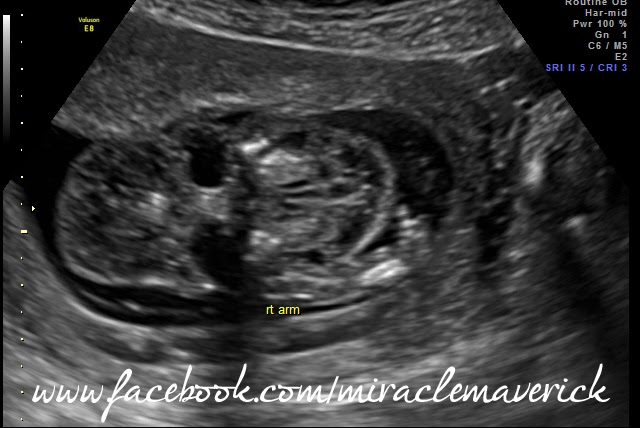

I started out confident. I relayed all medical information to the sweet nurse, Mary, and anxiously awaited the ultrasound. Minutes later I was watching the screen as the tech quickly took measurements. I wasn't exactly sure what I was looking at, but I had a sneaking suspicion that something wasn't quite right. When she took his skull measurement, I could see that there was a shadow behind his head of nearly the same size. I hoped it was just his abdomen. In less than 10 minutes, she was done. That alone was concerning, as I was told it would take an hour. A few minutes later the genetic councilor came in and him and I went over a lot of information that I already knew about. I more or less wanted him there to help Larry learn about what was going on.

Then things took a turn for the worst very quickly. The Maternal Fetal Medicine Specialist got straight to the point and informed us that they found several things on the ultrasound that were very concerning. At first I thought he was just confirming the Down Syndrome diagnosis, but when he brought up the first ultrasound image, my whole world was turned upside down. He told us that the nuchal translucency (fluid behind the neck) had gone from 2.8mm to 13mm in just 3 weeks, and that it now surrounded his whole body. He brought up the image that confirmed my fears, the "shadow" behind his skull that I had seen during measurements was in fact the fluid. He then showed us that baby had pleural effusion (fluid pooling) on his lungs and informed us that all these accumulations of fluid were very likely the result of severe heart defect. Although it was too early to do an echo on his heart, he was able to pull up an image of one minor defect already evident, an EIF of Echogenic Intracariac Focus, or a small mineral/calcium deposit. All these signs, combined with shortened femurs were a sure sign that he did in fact have Downs Syndrome, but suddenly that was the least of our worries.